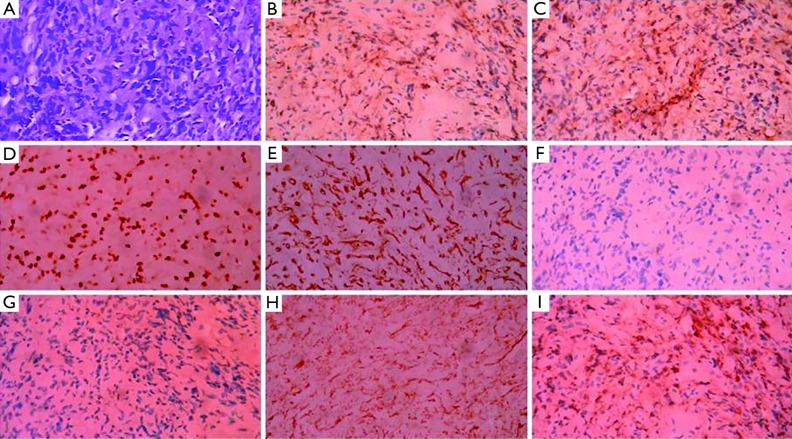

The pleural fluid was light yellow and highly cellular, in which 75% was mononuclear cells. Results from the analyses of the right side pleural fluid indicate an exudative type according to the Light criteria (3), which contained total protein 56.2 g/L, albumin 18.3 g/L, globulin 37.9 g/L, A/G 0.5, lactic dehydrogenase (LDH) 142.0 U/L, a-hydroxybutyrate dehydrogenase (aHBDH) 172.7 U/L, adenosine deaminase (ADA) 62.4 U/L. No acid-resistant bacilli were found. Computed tomography (CT) image of the chest (axial view) indicated bilateral sided pleural effusion and distinctive pleural nodular-like thickening as shown in Figure 1. The posteroanterior skull radiographs demonstrated low craniofacial bones density, and saccate transparent area could be seen without any signs of fractures. The posteroanterior view of pelvis was normal. The single photon emission computed tomography (SP-ECT) scan indicated metabolic disturbance of skull bones and elevated metabolism condition of the middle of left humerus.

Figure 1.

Computed tomography (CT) of the thorax before the chemotherapy: initial image showed bilateral pleural effusions (red arrows) and distinctive nodular-like thickening of bilateral pleural with apparent enhancement (black arrows).